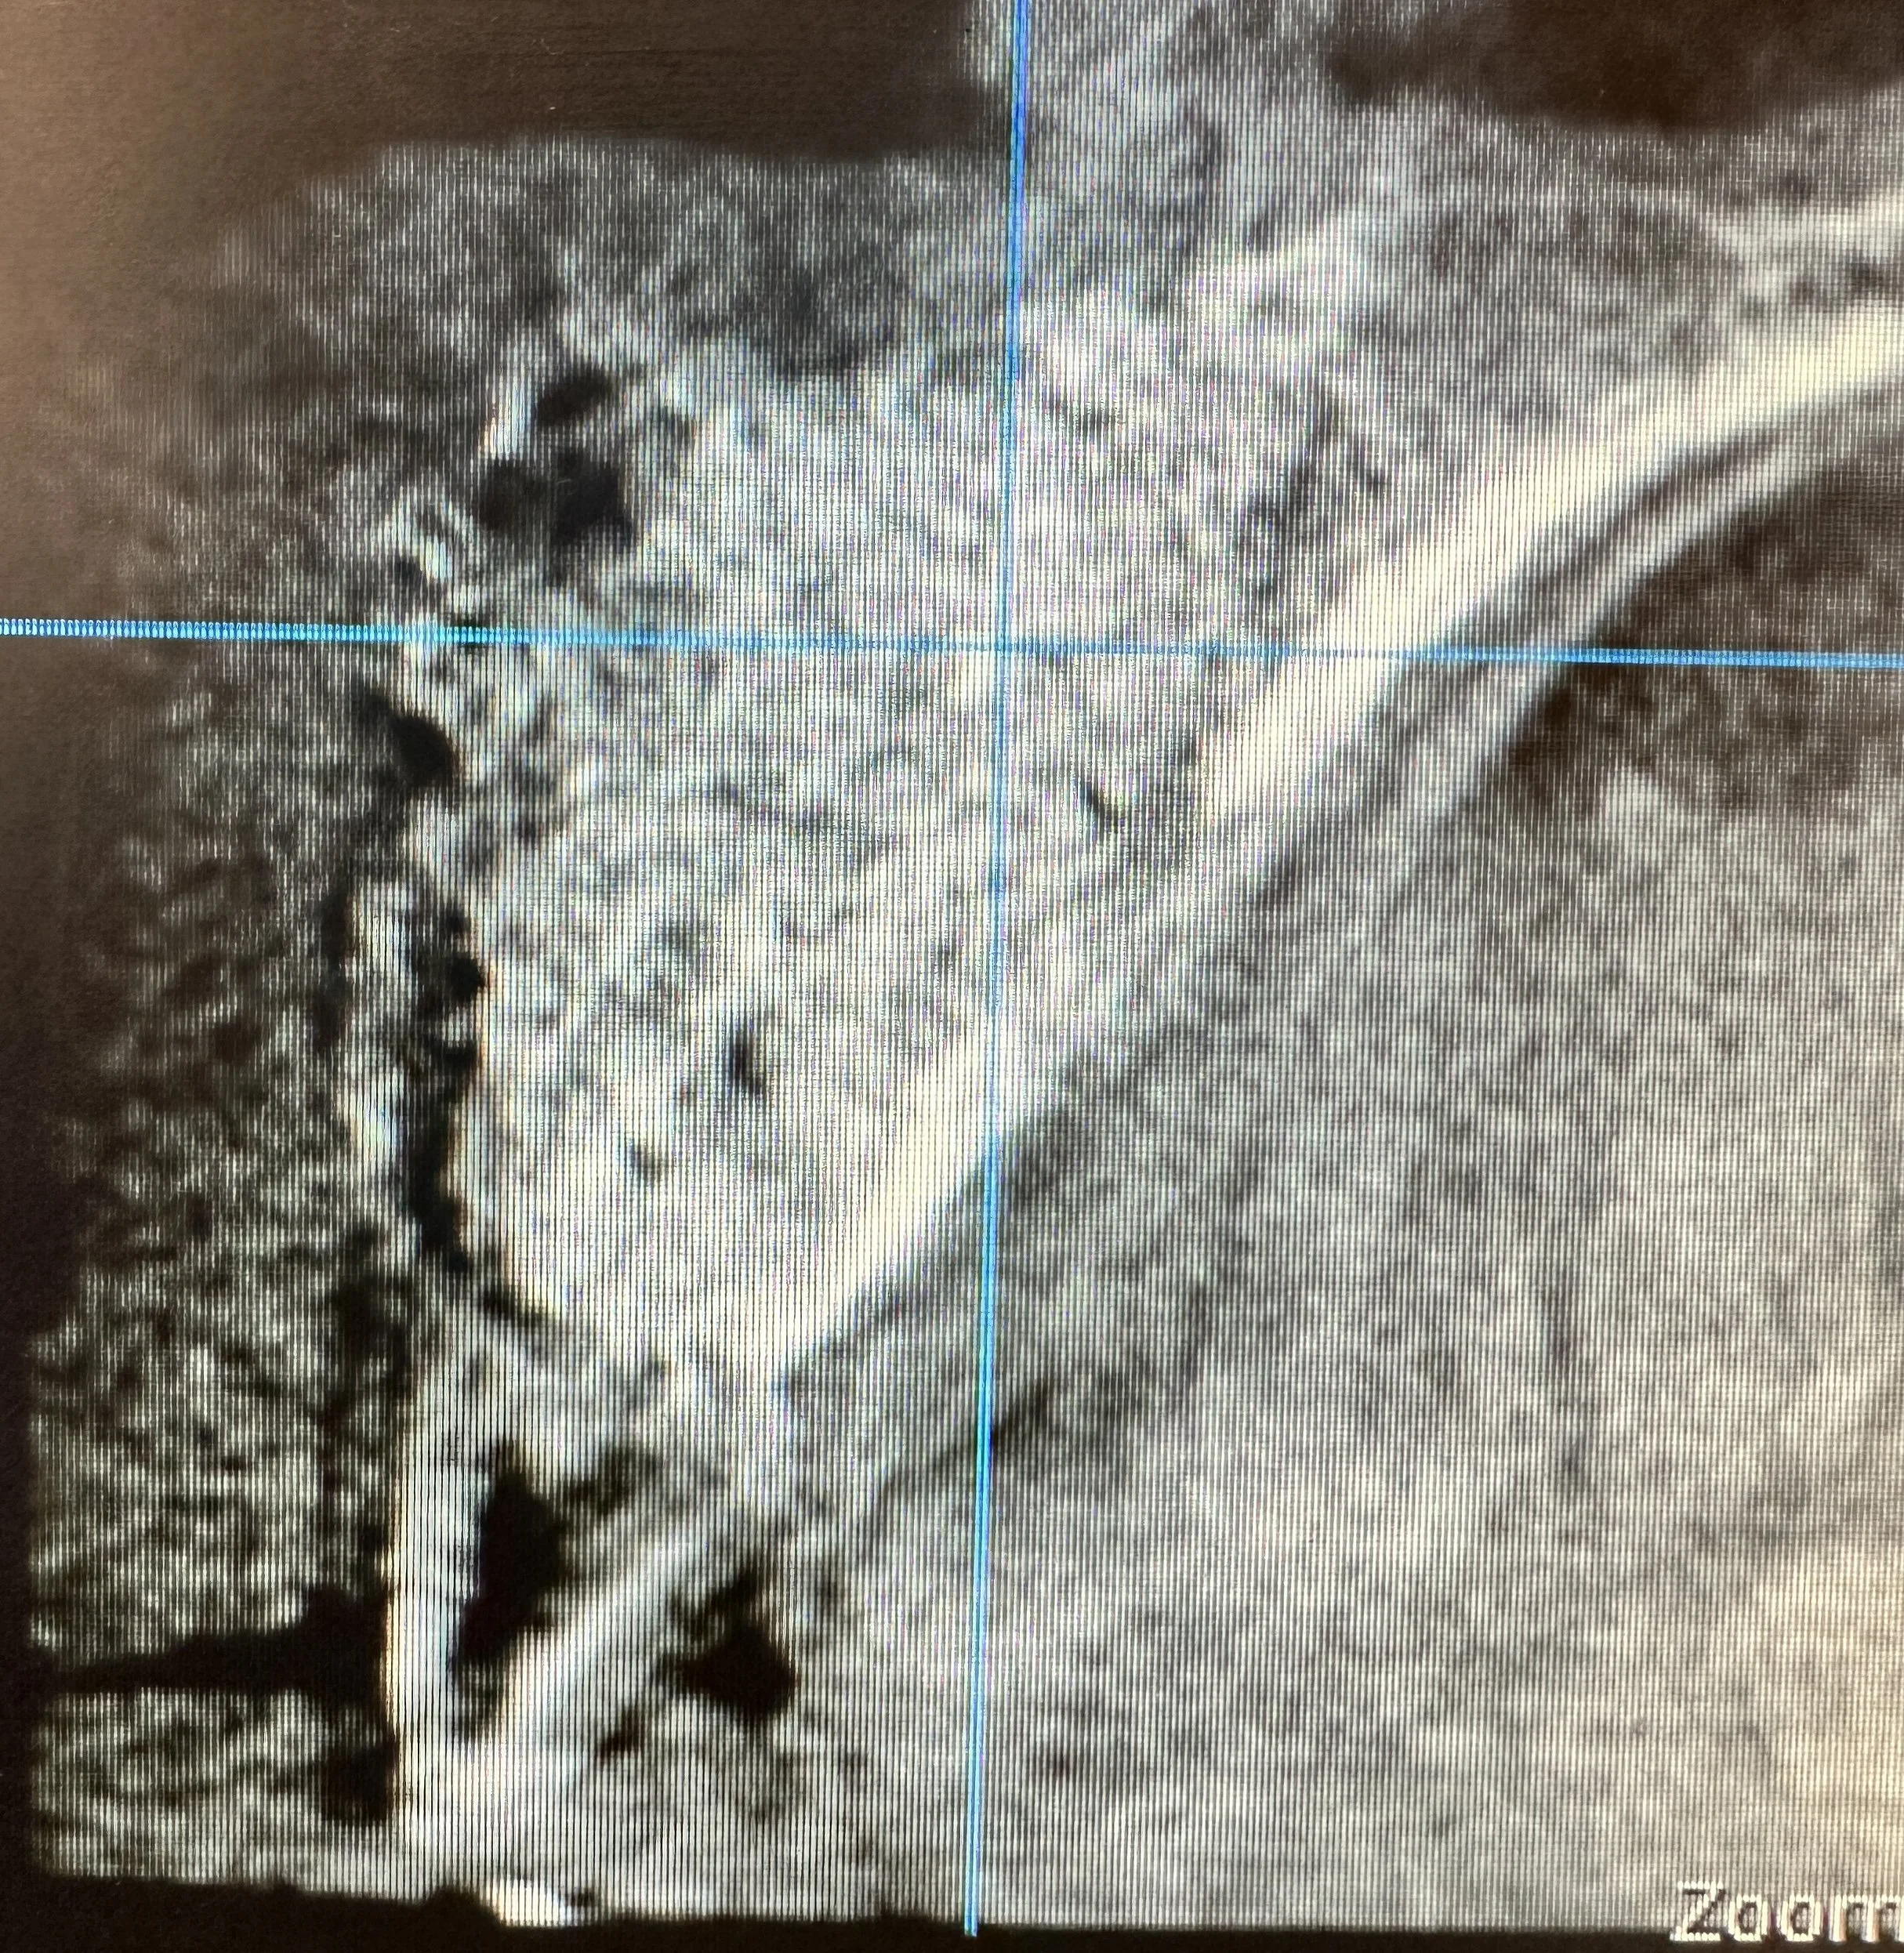

A patient presented with a large cystic lesion associated with tooth #8, resulting in significant bone loss extending from the apical third of the root to the nasal sinus floor. Advanced imaging also revealed mesial root resorption of tooth #8.

Tooth #8 was extracted, and the cyst was carefully enucleated. The extent of bone loss included destruction of the buccal bony wall and involvement of the palatal wall. To reconstruct the site and preserve the ridge architecture, a resorbable collagen membrane was first placed along the palatal wall. A mineralized cortico-cancellous particulate bone graft was then gently packed into the area of bone destruction to restore volume and support future regeneration.

Post-operative CT imaging confirmed successful placement of the graft material in the previous area of bone destruction. The resorbable membrane served to prevent soft-tissue ingrowth and maintain graft stability during the healing phase, allowing bone turnover to occur gradually as the graft resorbed and new bone formed.